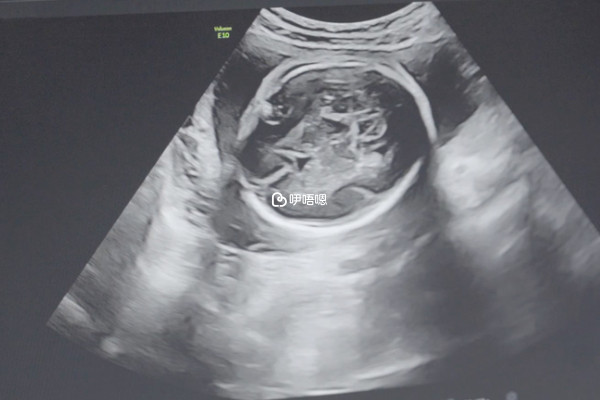

其實不管是做試管嬰兒還是自然懷孕,其實都會發生胎停育,它的意思就是胚胎髮育到某個階段之後就不再發育或者是死亡,通常造成這一現象的原因有很多,下面就說說做試管嬰兒如何防止胚胎停育:

胚胎停育多是由於胚胎本身存在染色體異常,無法正常發育所致。因此,對於孕婦自身或其丈夫存在染色體異常等遺傳缺陷者,發生胚胎停育的風險會大大增加,應該在試管前進行遺傳諮詢,減少胚胎停育的發生。